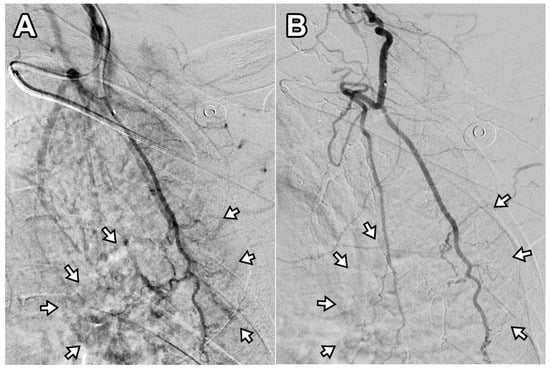

3.2. Pain Changes After TAE

Two patients required a second TAE procedure due to persistent pain at 75 and 41 days after the initial treatment. A total of 12 TAE procedures were performed in 10 patients, achieving a technical success rate of 100% (12/12). On average, 1.8 ± 0.9 arterial branches were embolized per procedure, and 171 ± 54.2 mg of IPM/CS was used per TAE. An illustrative case is presented in Figure 2. Following TAE, the NRS score significantly decreased to 2.1 ± 0.7 at 1 month, 2.0 ± 1.1 at 3 months, and 1.9 ± 1.2 at 6 months (p < 0.001). Clinical success, defined as an NRS reduction of ≥50% from baseline, was achieved in 90% (9/10), 100% (10/10), and 90% (9/10) of patients at 1, 3, and 6 months, respectively. The reduction in NRS score after TAE was significantly greater at 1 month, 3 months, and 6 months when compared with the last follow-up data of the injection-only group (p = 0.024, 0.005, and 0.006, respectively). The percentage of NRS score change was −70.2%, −73.4%, and −74.8% at 1, 3, and 6 months post-TAE, showing no significant difference compared with the last follow-up data of the injection-only group (−69.7%; p = 0.931, 0.486, and 0.397 at 1, 3, and 6 months post-TAE, respectively). The changes in NRS score over time are illustrated in Figure 3. A detailed comparison of pain score reductions and percentage changes between groups following injection and TAE is shown in Table 2. Detailed individual patient-level data, including baseline NRS, pain duration, type of injection, TAE details, and follow-up NRS, are provided in Table S1.

Figure 2. Digital subtraction angiography of the deep branch of the left transverse cervical artery in a 56-year-old woman with refractory interscapular pain. (A) Pre-embolization image shows abnormal neovascularization in the interscapular area (arrows). (B) Post-embolization image demonstrates disappearance of abnormal blush in the corresponding area (arrows). This patient experienced a decrease in NRS score from 6 to 2 at 6-month follow-up (67% reduction).